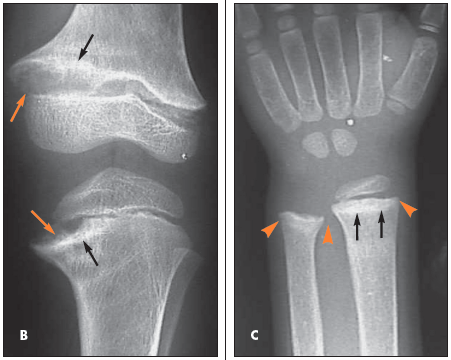

The radiograph of the knees shows bilateral genu varum and widening of all the tibial and femoral physes (A, orange arrows); there is also prominent sclerosis adjacent to the physes, primarily located in the medial portions of the metaphyseal tibiae and femora (A, black arrows). The radiograph of the left knee better demonstrates the physeal widening (B,orange arrows) and the juxtaphyseal sclerosis (B, black arrows). The radiograph of the left wrist shows widening of the distal radial physis with flaring of the distal radial and ulnar metaphyses (C,orange arrowheads); sclerosis adjacent to the radial and ulnar physes is most prominent in the distal radial metaphysis (C, black arrows). A prominent anterior costochondral junction caused by the preponderance of the maturing cartilage can also occur in persons with rickets.